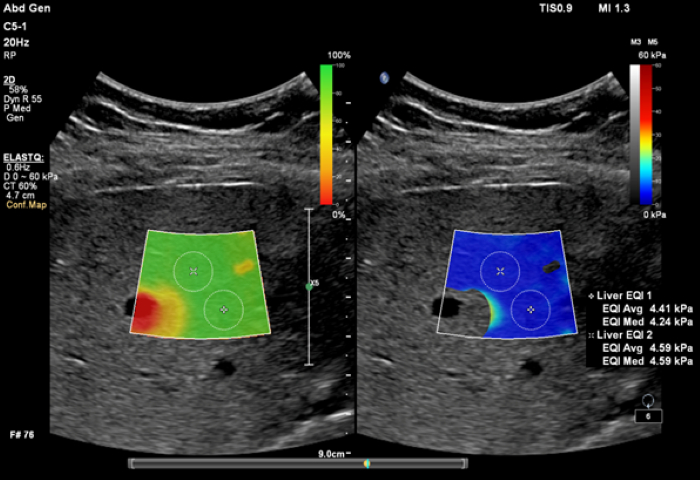

ElastQ imaging is a real-time, large Region of Interest (ROI), color-coded quantitative assessment of tissue stiffness. It is the only solution to offer both PureWave technology and high frame rate real-time shear wave imaging across abdominal applications. Clinicians can easily assess liver tissue stiffness using real-time feedback and make quantitative measurements with multiple sample points even retrospectively on DICOM stored images. Unique confidence map, used with the stiffness map, improve confidence of shear wave measurements. Both maps can be displayed side-by-side, which reduces workflow steps and allows for simultaneous map correlation during acquisition and measurement phases.